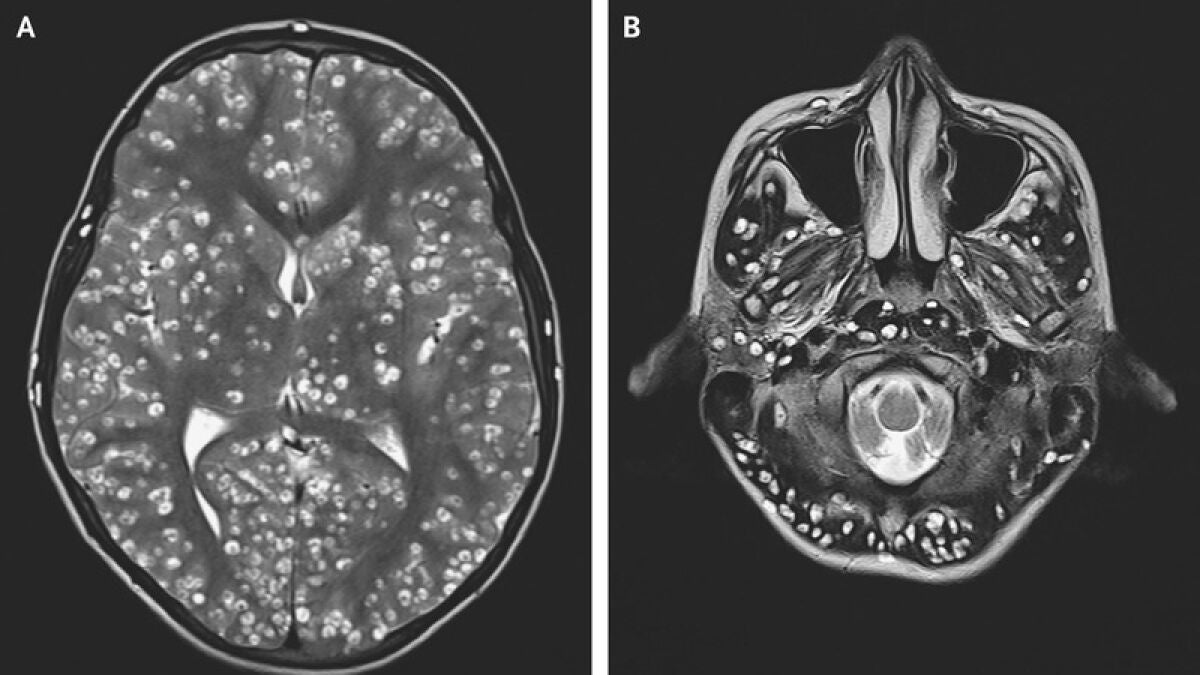

Los médicos creían que la paciente padecía un cáncer cerebral y, tras una operación, descubrieron que lo que realmente había en su cabeza era una tenia de cerdo.

El médico de la mujer detectó una pequeña lesión en el lóbulo frontal izquierdo de su cerebro y la derivó al doctor Jonathan Rasouli, del hospital Mount Sinai en Nueva York.

La joven se sometió a una operación para extirpar el tumor. Durante la cirugía el neurocirujano vio "una lesión bien encapsulada y firme que era ovoide". "Parecía un huevo de codorniz", afirma Rasouli. En ese momento el médico descubrió que no se trataba de un tumor cerebral. El doctor cogió una muestra de la lesión extraída, la colocó bajo un microscopio quirúrgico y descubrió que lo que tenía era una tenia de cerdo.

Esta enfermedad es poco común, los que corren más riesgo de sufrir esto son las personas que viajan a países donde la tenia de cerdo es endémica y comen alimentos crudos contaminados, como pueden ser frutas, verduras o carne de cerdo cruda.